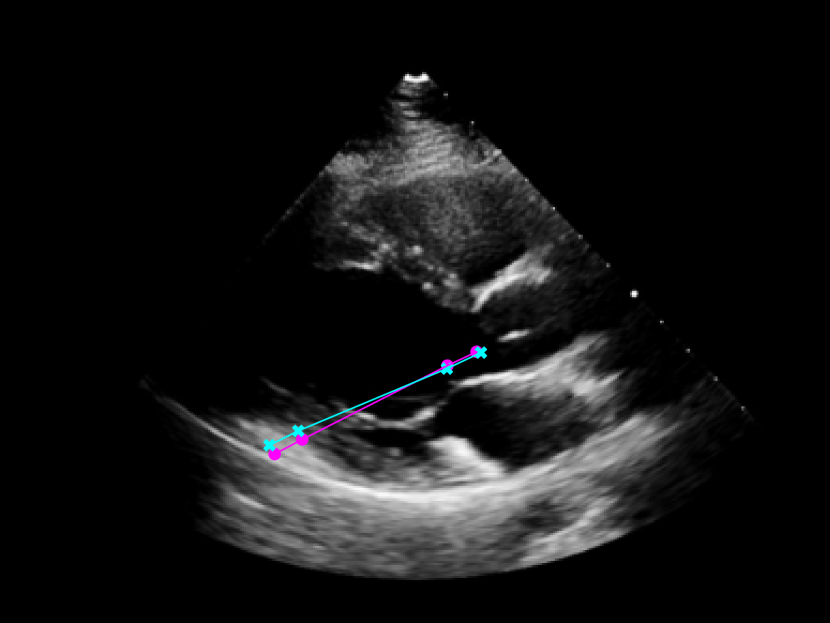

As seen in Figure 4, the model was trained to identify four key points in the echocardiogram videos: the beginning and end of the intraventricular septum (IVS), and the beginning and end of the left ventricular posterior wall (LVPW). These points were used to calculate the lengths of the IVS and LVPW, and the internal diameter of the left ventricle (LVID).